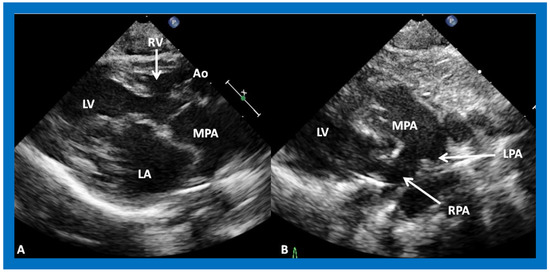

Figure 11. (A) A selected video frame from parasternal long axis views of a patient with tricuspid atresia and transposition of the great arteries demonstrating the left atrium (LA), left ventricle (LV), a very small right ventricle (RV) and a moderate sized ventricular septal defect (not marked). The vessel coming off the LV is traced in (B) and shown to bifurcate into the left (LPA) and right (RPA) pulmonary arteries, confirming that this vessel is the main pulmonary artery (MPA), consistent with transposition of the great arteries. Ao, Aorta. Reproduced from Reference [29].

Applsci 11 09472 g011

Figure 12. A selected video frame from a parasternal long axis view with color flow mapping of another patient with tricuspid atresia and transposition of the great arteries demonstrating the left atrium (LA), left ventricle (LV), a small right ventricle (RV) and a moderate sized ventricular septal defect (VSD). The vessel coming off the LV bifurcates into right (RPA) and left (LPA) pulmonary arteries. Reproduced from Reference [29]. PA, pulmonary artery.

Applsci 11 09472 g012

The relationship of the great arteries is examined next in order to classify them into various types, as mentioned above. The relationship of the great arteries (Figure 2, top) is established by following the vessels arising from the ventricles until the pulmonary artery (PA) bifurcation or aortic arch. In Type I patients with normally related great arteries, the aorta arises from the LV (Figure 10) and in Type II patients with transposition of the great arteries, the PA arises from the LV (Figure 11; Figure 12). In Type II patients, the blood vessel arising from the LV should be traced to demonstrate its branching into the right and left PAs (Figure 11; Figure 12). In Type III patients, it may be a little more difficult to assign the great artery relationship and, sometimes, other imaging studies, including angiography, may be needed to define the great artery relationship. In Type IV with truncus arteriosus, the limited data suggest that this can be performed by echocardiography (Figure 13; Figure 15). In the example shown [31], the atretic tricuspid valve (Figure 13a and Figure 14a), VSD (Figure 13b and Figure 14b), hypoplastic RV (Figure 14a), single vessel (truncus) arising from the heart (Figure 13c,d, and Figure 14c,d), and origin of the PA and its division into branch PAs (Figure 13d, and Figure 14c,d) were demonstrated.